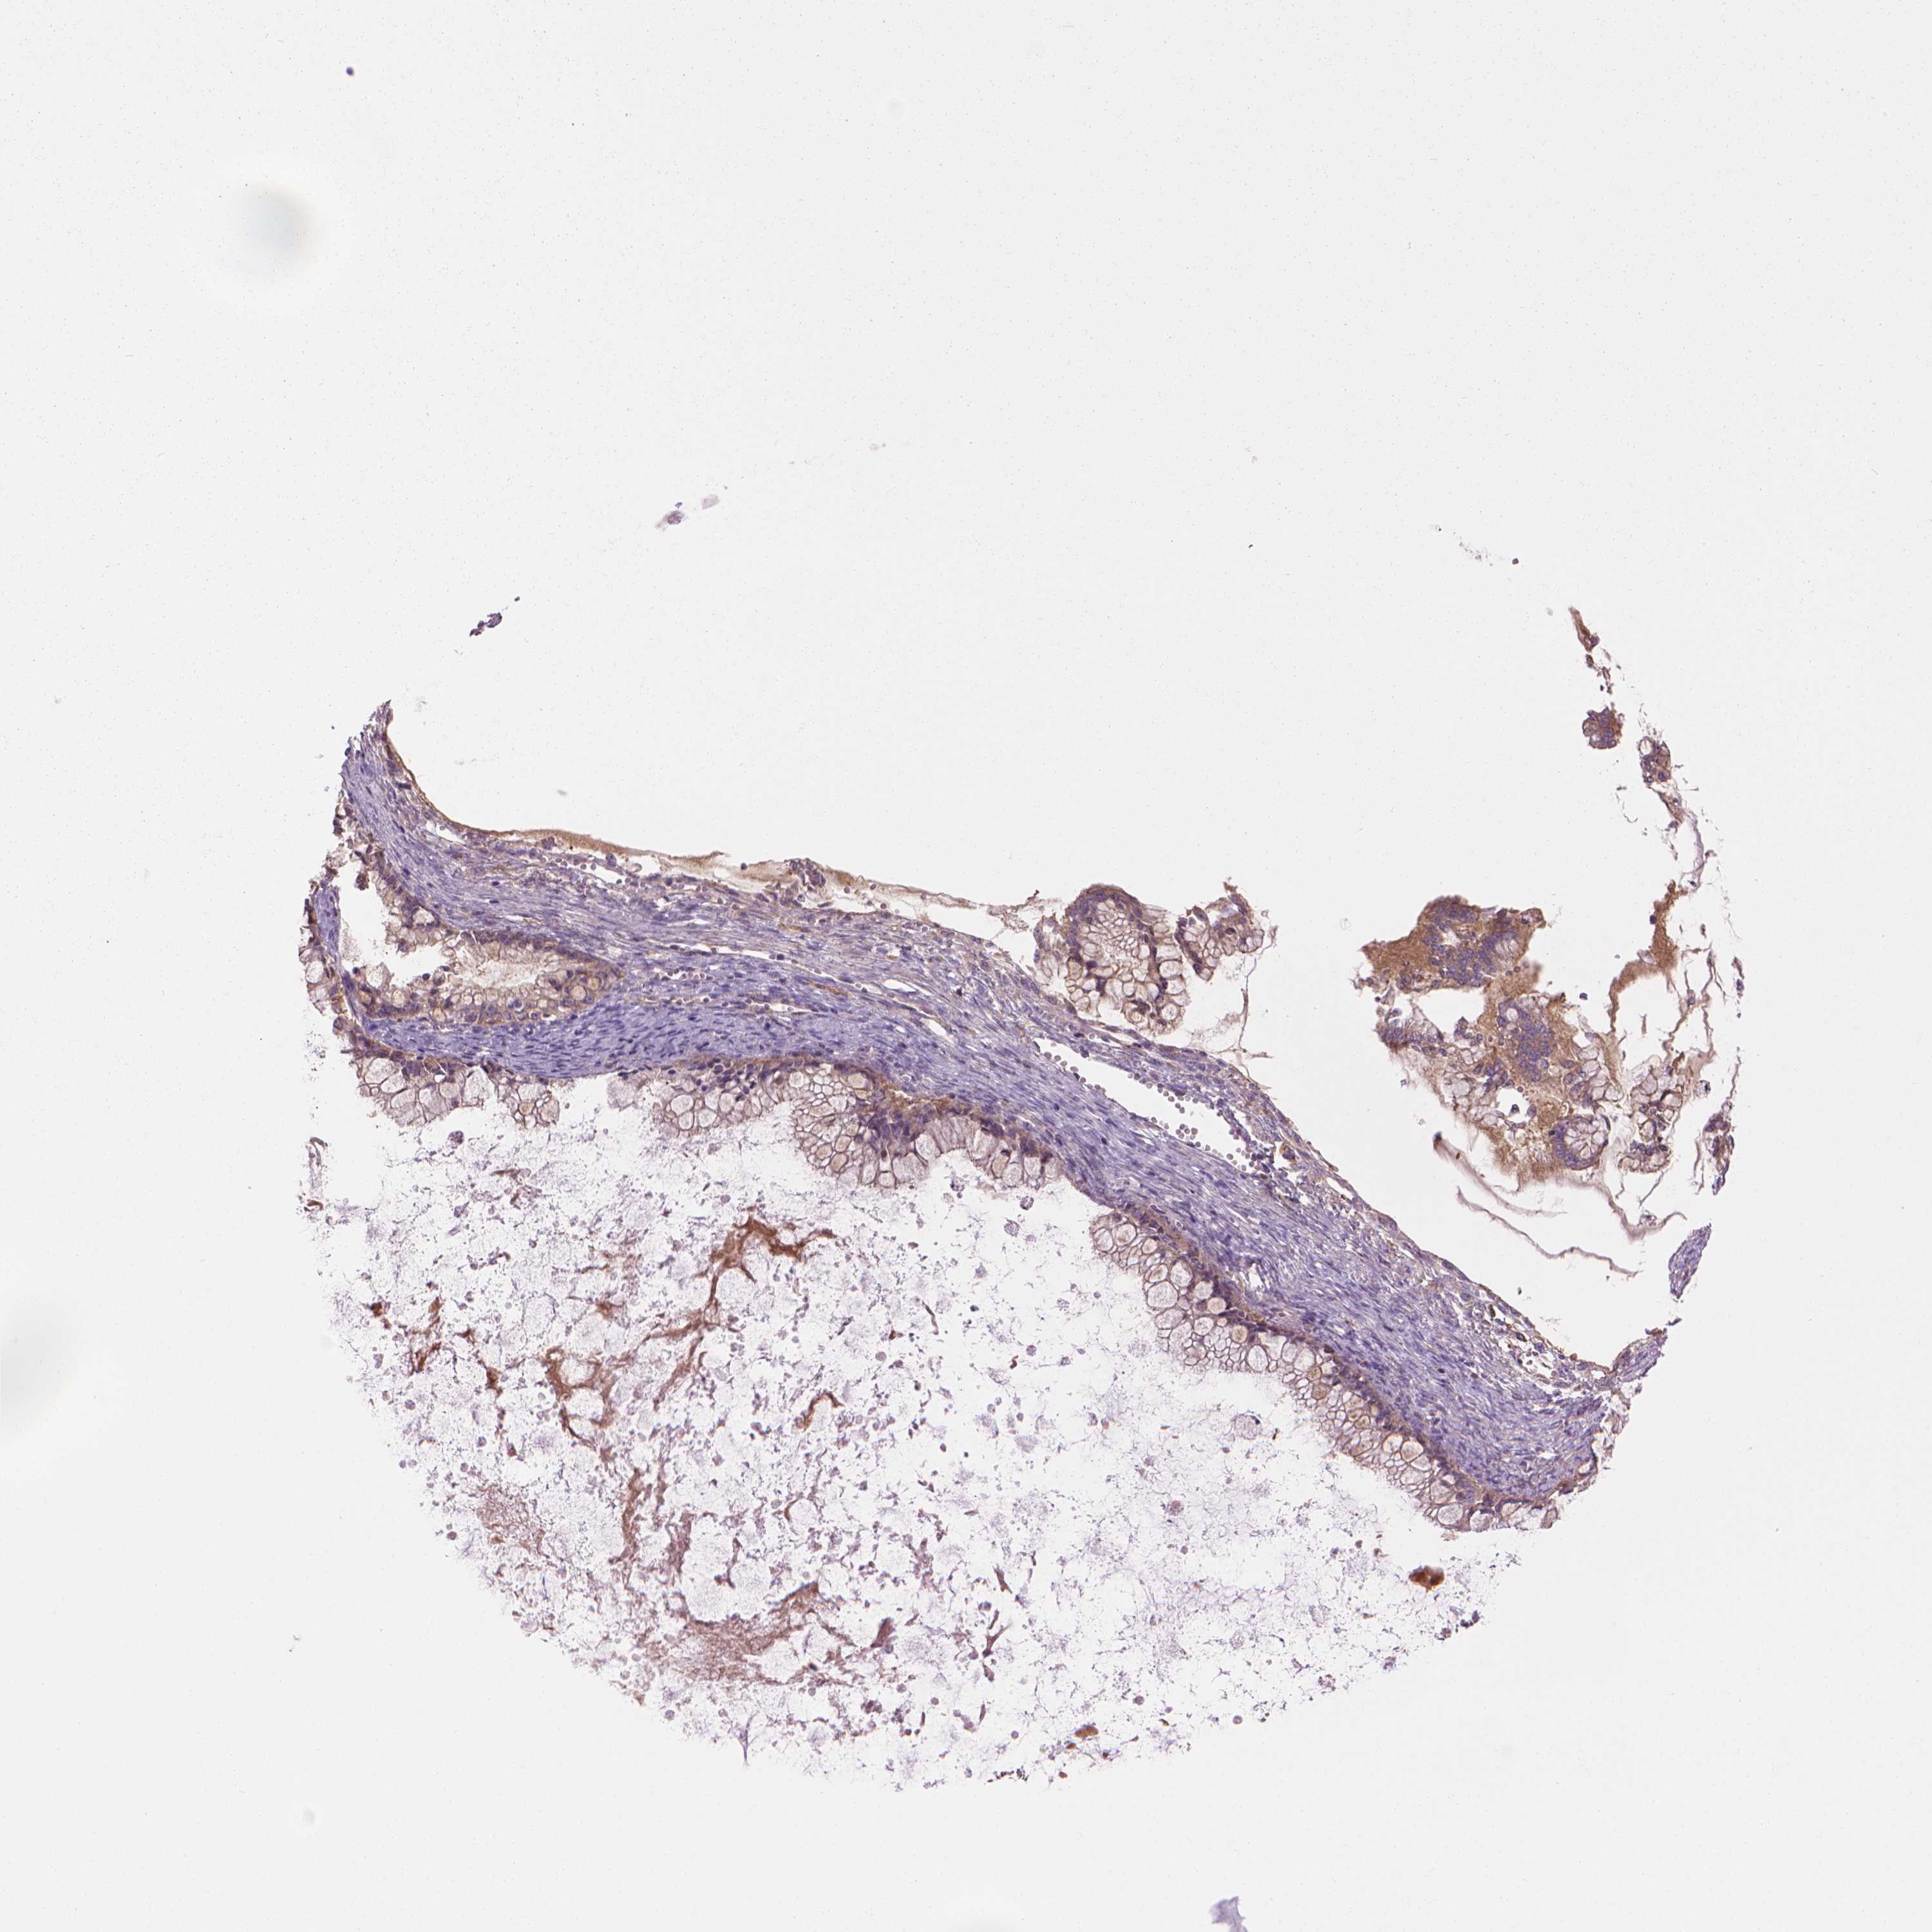

OVARIAN CANCER - Protein expressioni

A mouse-over function shows sample information and annotation data. Click on an image to view it in a full screen mode. Samples can be filtered based on level of antibody staining by selecting one or several of the following categories: high, medium, low and not detected. The assay and annotation is described here.

Note that samples used for immunohistochemistry by the Human Protein Atlas do not correspond to samples in the TCGA dataset.

Antibody stainingi

Antibody staining in the annotated cell types in the current human tissue is reported as not detected, low, medium, or high, based on conventional immunohistochemistry profiling in selected tissues. This score is based on the combination of the staining intensity and fraction of stained cells.

Each image is clickable and will lead to virtual microscopy that enables deeper exploration of all samples and also displays staining intensity scores, fraction scores and subcellular localization as well as patient and tissue information for each sample.

Antibody HPA070456

Antibody CAB017616

Staining

High

Medium

Low

Not detected

Intensity

Strong

Moderate

Weak

Negative

Quantity

>75%

75%-25%

<25%

None

Location

Nuclear

Cytoplasmic/membranous

Cytoplasmic/membranous,nuclear

Cystadenocarcinoma, serous, NOS

Cystadenocarcinoma, mucinous, NOS

Carcinoma, endometroid

Carcinoma, NOS